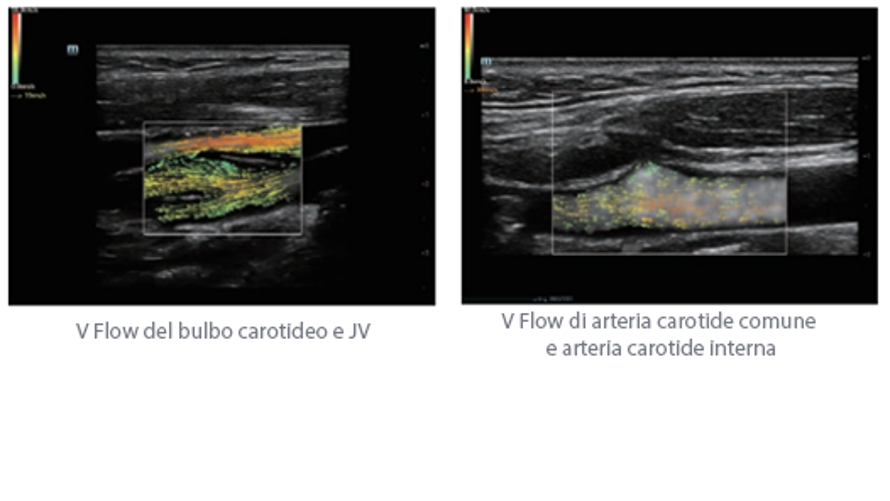

Oltre alla qualit├Ā delle immagini di livello eccellente, Resona 7 migliora anche le capacit├Ā di ricerca clinica il rivoluzionario V Flow per la valutazione emodinamica vascolare, e l'acquisizione piani pi├╣ intelligente dal set di dati 3D per la diagnosi del sistema nervoso centrale fetale. Combinando il pi├╣ intuitivo funzionamento multi-touch basato su gesti e tutte le caratteristiche cliniche essenziali, Resona 7 sta veramente portando nuove tendenze nellŌĆÖinnovazione dellŌĆÖecografia.